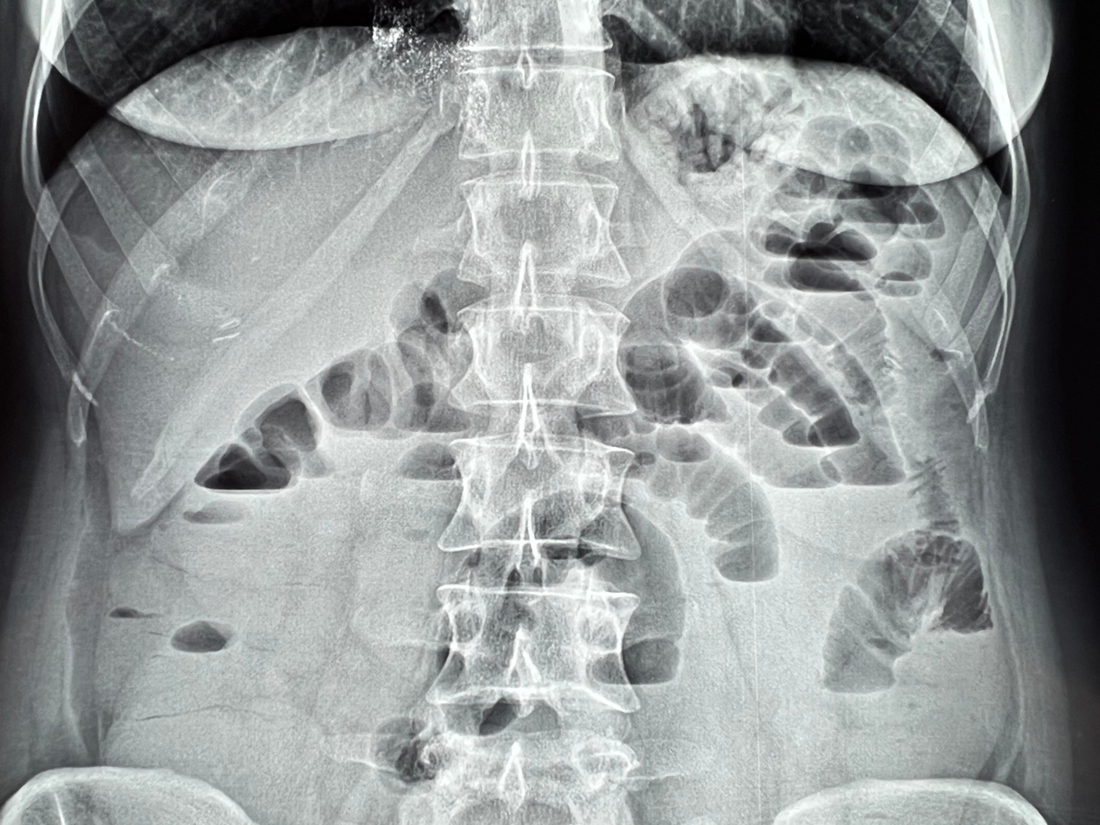

そこで研究チームの柴田氏が動物の腸を縛って、人工的な閉塞を起こさせる実験を行いました。

動物の腸を一カ所縛り、食物が腸を通り抜けることができない状態にすると、動物は嘔吐したり腹痛を訴えたり、非常に苦しみ死んでいきますが、死ぬ前に脳髄を調べると、必ず脳髄に出血が起こっていることが確認できました。

次に、この腸閉塞を起こした動物の閉塞部の腸内容物を採取してこれを滅菌し、健全な動物に注入してみると死にいたります。

死んだ動物の脳髄を調べてみると、やはり出血が起こっているのです。

ということは、この腸閉塞症の腸内容物に含まれる毒素が、脳髄に出血を起こさせていることになります。